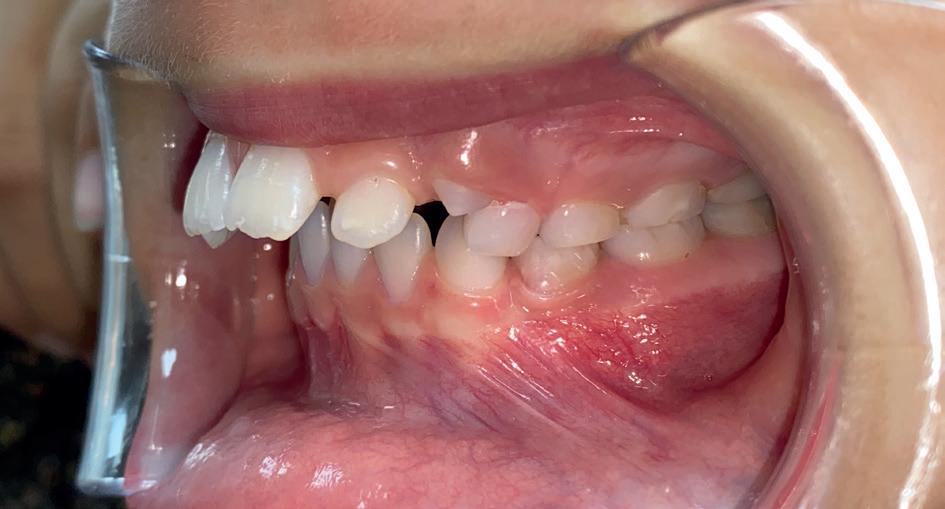

Casus: uit de Praktijk Sole & Jalissa.

Eén overbeet, twee gezichten

Sole en Jalissa kwamen op jonge leeftijd bij ons in de praktijk. Op het eerste gezicht leken hun gebitten totaal verschillend, maar achter de lach ging dezelfde afwijking schuil: een overbeet van 9–10 mm en versmalde tandbogen.

Bij Jalissa was de Klasse II-relatie direct zichtbaar: de bovenkaak stond duidelijk vóór de onderkaak en de lippen sloten moeilijk.

Bij Sole leek het minder opvallend. Haar bovenste snijtanden (11/21) stonden namelijk naar binnen gekanteld (Klasse II Divisie 2), waardoor de overbeet gecamoufleerd werd – maar de kaakrelatie was identiek.

Dit soort casussen laten zien waarom het belangrijk is om verder te kijken dan alleen de zichtbare tandstanden. Wat aan de buitenkant mild lijkt, kan functioneel en skeletaal net zo ernstig zijn.

Behandeling – starten met de juiste basis

Beide meisjes begonnen met een Twinblock-beugel, een functioneel apparaat dat de groei van de onderkaak stimuleert en de overbeet corrigeert. Ze droegen deze 9 tot 12 maanden.

Deze fase zorgde voor:

• Voorwaartse groei en positionering van de onderkaak

• Verbetering van de lip- en profielbalans

• Ruimte in de kaakbogen door natuurlijke verbreding

• Voorbereiding op een voorspelbaar verloop met vaste apparatuur (slotjesbeugel)

Na deze fase kan de slotjesbeugels efficiënt starten.

Waarom timing belangrijk is

Wij adviseren om een Twinblock te starten rond eind groep 6 of begin groep 7. In deze periode:

• is de groeispurt optimaal te benutten,

• is de motivatie hoger (voor middelbare school),

• en kan een operatie of complexe behandeling op latere leeftijd vaak worden voorkomen.

Te laat starten – bijvoorbeeld in de brugklas – betekent meestal minder groei, minder motivatie en grotere behandeluitdagingen.

Overbeet: 9 - 10 mm bij beide

Kaakrelatie: Klasse II (Jalissa)

Klasse II Div. 2 (Sole, 11/21 retrogekanteld)

Tandbogen: Versmald

Eerste behandeling: Twinblock, 9 - 12 maanden

Doel: Kaakrelatie corrigeren, profiel

verbeteren, ruimte creëren

Resultaat: Zachter profiel, betere balans, goede basis voor slotjesbeugel